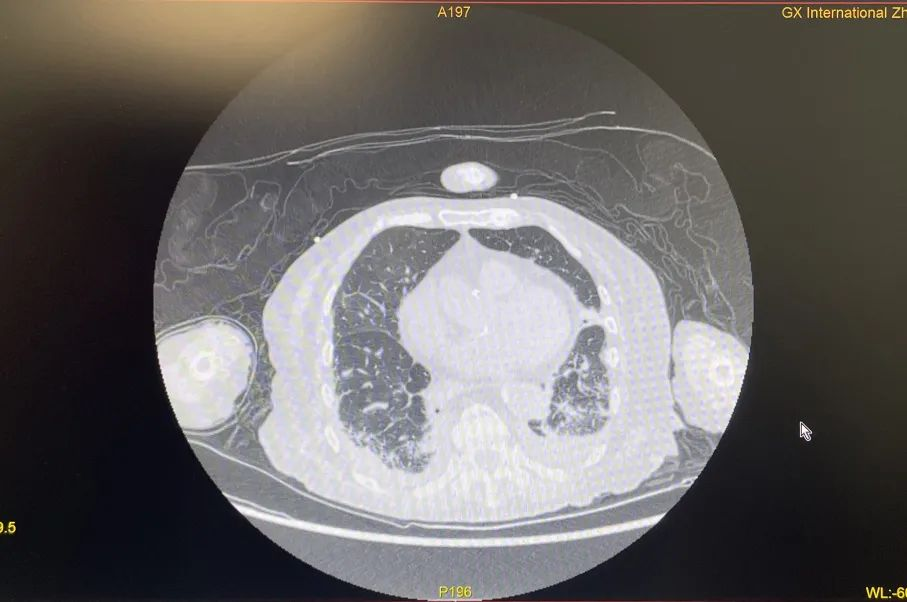

2022年12月末,87岁的胡奶奶因“气喘、咳嗽”等症状到国壮肾病科就医,被发现血氧低下和新型冠状病毒感染,经CT进一步检查发现其肺部感染严重。

胡奶奶肺炎程度高,氧合指数、氧分压极低。